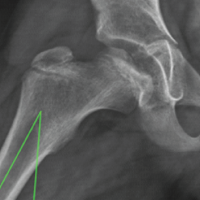

A 71-year-old Caucasian woman presented to our orthopedic department due to chronic right knee pain, which had worsened over the past year. Clinically, mild valgus knee deformity of approximately 10° was observed. Her medical history included arterial hypertension, dyslipidemia, and osteopenia, with a body mass index of 33. She was diagnosed with the right knee osteoarthritis (Fig. 1) and was scheduled for a TKA.

In general, the risk factors for patellofemoral joint instability after total knee replacement can be categorized into three groups, component positioning and surgical technique, soft-tissue balancing, and other causes [1,2,3,6]. In our patient, the femoral and tibial components were found to be correctly placed on the CT scan. The patient had a mild valgus knee joint alignment of approximately 10°. As described in the literature, valgus knees are predisposed to patellar instability [2,7]. In cases of valgus deformity, the posterior cruciate ligament is often contracted, making it more difficult for the surgeon to correct the deformity.[8] In addition, posterior-stabilized components tend to be more stable and can be more lateralized to improve patellar tracking in the trochlear groove [9,10,11]. This is why we decided to use a posterior-stabilized total knee replacement in our patient, along with the fact that the medial retinaculum appeared very thin. There is also a greater risk of soft-tissue imbalance in patients who undergo a medial parapatellar approach [1,12]. We believe that in our patient, the main factors contributing to secondary post-operative patellar subluxation were the valgus malalignment, which led to chronic imbalance with a fragile medial retinaculum and chronic impingement of the lateral facet of the patella where the bony prominence was found. Due to the thinned and fractured patella, we chose not to reconstruct the medial patellofemoral ligament, even though excellent results are reported in the literature [1,13]. We also avoided distal realignment due to the risk of material failure, nonunion, patellar tendon rupture, and osteonecrosis of the fragment, especially after a cemented TKA in an osteopenic patient [1,2]. Hence, we proceeded with proximal realignment using the Insall procedure [1], which appeared to be safer [2] for the patient, along with a lateral retinaculum release. In addition, due to the removal of the fractured lateral facet, we performed a lateral facectomy, which in combination seem to have good results for patellar instability after TKA [1,12].